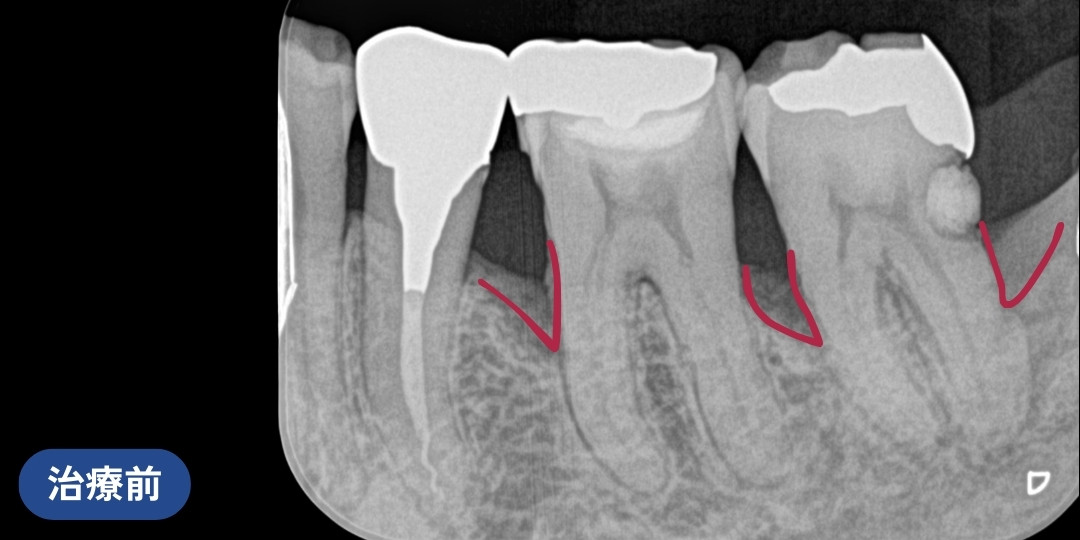

中等度歯周病を保険診療で再生治療した症例(40代女性)

歯周病の治療をしたいと来院されました。

歯周基本治療を行い、保険適用のリグロスを用いた歯周組織再生療法を行いました。

診断の結果、レントゲンが黒くなっている部分があり、骨が吸収されていました。中等度の歯周病です。

歯周基本治療を行い、歯周組織再生療法を行いました。

リグロスは、歯周組織の再生効果がある薬剤です。

同じ成分が皮膚科の皮膚再生にも使われています。

歯肉を切開して、治療箇所に薬剤を注入する外科的処置です。